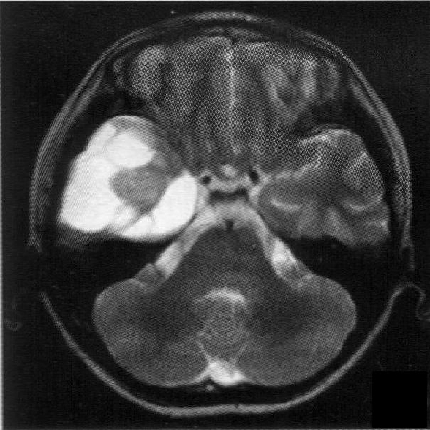

标题: PED1818:男,13岁。头痛5天,复视、呕吐3天。体检:神经生 [打印本页]

标题: PED1818:男,13岁。头痛5天,复视、呕吐3天。体检:神经生

右中颅窝见囊性占位影,其中央见块状高密度影,高密度块后后缘见条状钙化?前部与殘存颞叶皮质相连,临近骨质无异常,病灶囊变区呈长t1长t信号,实性区呈中等信号,增强(最后两副是增强t1像吧)有明显强化,实性块影上部尚见鸟嘴状影(比较像脑膜尾),考虑右中颅窝脑膜瘤可能性大,不排除室管膜瘤,畸胎瘤等

病理:囊性脑膜瘤